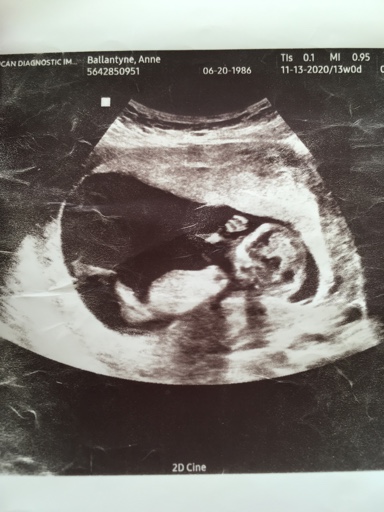

13 week ultrasound pics

Attachment 43309

Attachment 43310

Attachment 43311